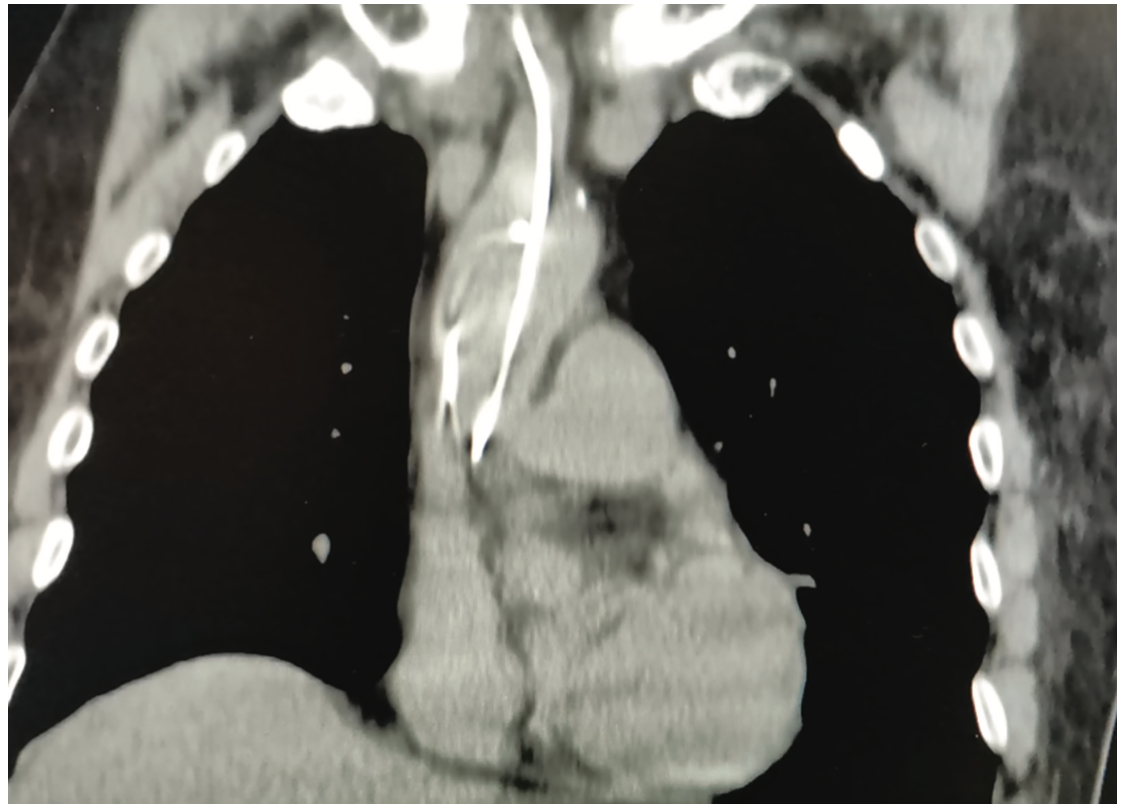

We report the case of a 77-year-old male who underwent temporary pacemaker lead implantation after a symptomatic 2:1 Mobitz type II second-degree block and left bundle branch block conduction (Figure 1). The temporary pacemaker was implanted apparently through the right jugular vein without fluoroscopic guidance, only by monitor guidance. After medical stabilization the patient was referred to our tertiary care center for further management. A cardiovascular system examination was unremarkable. Electrocardiogram showed a paced left bundle branch block pattern; however, with a high threshold stimulation level. The x-ray showed an abnormal lead path (Figure 2). A computed tomography angiography was performed that documented an intra-arterial lead with entry into the right common carotid artery and with the tip crossing the aortic valve and ending in the left ventricular outflow tract (Figure 3). Removal of the lead and relocation of the temporary pacemaker was requested by interventional cardiology. The fluoroscopy showed a temporary pacemaker lead with an arterial course with a loop in the ascending aorta and the tip crossing the aortic valve (Figure 4). A puncture of the right common femoral vein was performed, and a 6 French introducer sheath was placed. The temporary pacemaker lead was advanced to the right ventricle (Figure 5). The intra-arterial lead was removed and an angiogram was performed through the introducer sheath, confirming the arterial site (Figure 6). The introducer sheath was subsequently removed without complications.

Video 1 (corresponding to Figure 3). A computed tomography scan documented an intra-arterial lead with entry into the right common carotid artery, with the tip crossing the aortic valve and ending in the left ventricular outflow tract.

In this case, the temporary pacemaker lead was unintentionally malpositioned through arterial access, suspected due to a high threshold stimulation level. An x-ray and computed tomography scan confirmed an abnormal lead path.

Early recognition required careful reading of the 12-lead surface electrocardiogram pacing morphology and other imaging modalities, including chest x-ray, computed tomography, and fluoroscopic images.